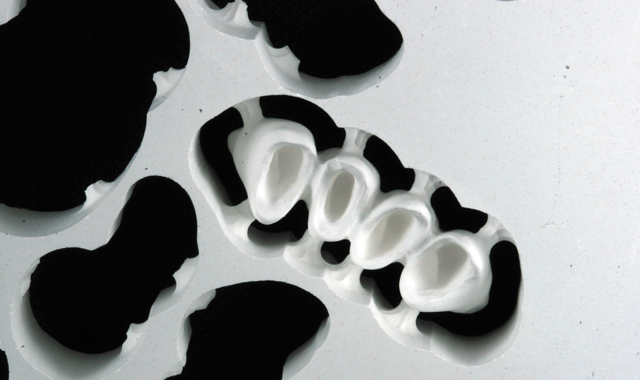

The file was sent to the Zenotec mill, and a Zenostar MT zirconia puck was selected, after which the design file was nested in the puck (Fig. 10). However, at the same time that the restoration CAD .stl file was sent to the laboratory for milling, the file was also used to enable production of a 3D-printed model with removable dies for verifying the proximal and occlusal contacts of the final

restorations. Then, when the milled restorations were completed, they could be tried and characterized on the printed model, then glazed and hand polished.

Prior to milling, the software created a simulation of the milled construction. This allowed the user to check for undercuts and preview the tool path (Figs. 11 and 11a). The Zenotec Hybrid Select then completed the milling of the zirconia construction (Fig. 12).